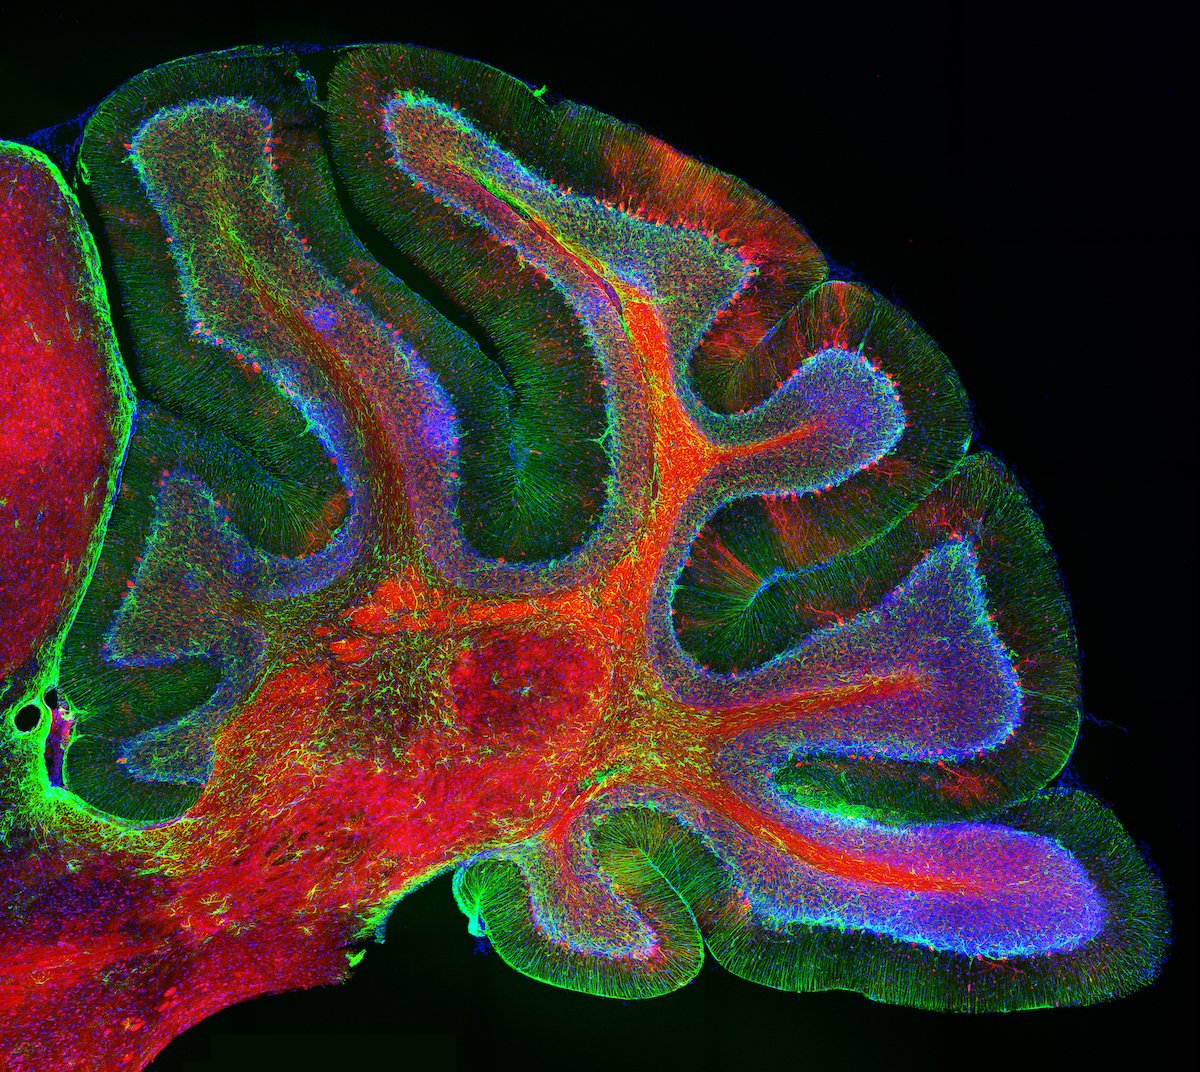

This image shows the cerebellum, a region of the brain important for motor coordination and predictive coding. It was taken by David Brann, and awarded second place in the 2018 Quad Photo Contest. Read more about the image here: http://hvrd.me/o49O30kEwCW pic.twitter.com/ixVHSmFxl2

That's beautiful (cerebellar anatomy always is!). Do I spy banding in those Purkinje cells?pic.twitter.com/uv6oE5Qzds